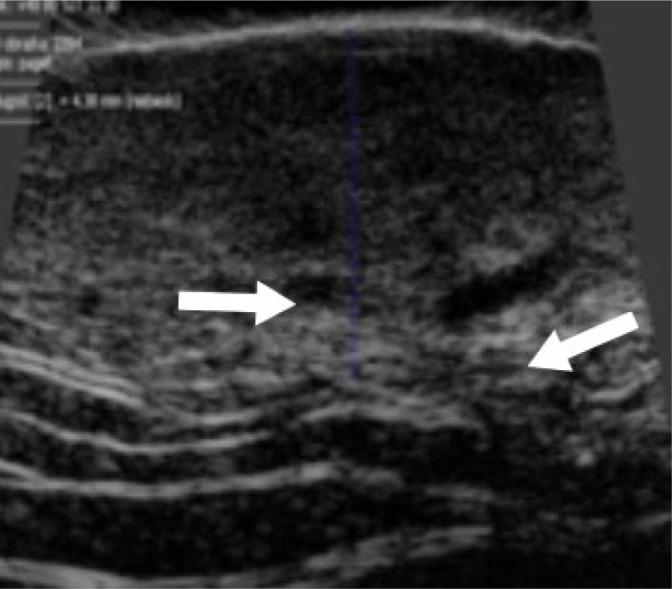

Paget's disease of the vulva is a rare skin cancer accounting for less than 1% of all vulvar neoplasias. Surgery is the first treatment of choice. Unfortunately, it is insufficient in many cases, which require further treatment, and the risk of recurrence is high. We present a case of an 85-year-old woman who underwent surgery due to Paget's disease of the vulva. A preoperative skin imaging using a high-frequency 48 MHz mechanical probe was used to assess the lesion margins. Typical high-frequency ultrasonographic features of vulvar Paget's disease were identified and analyzed. This is the first report of high-frequency ultrasonography imaging of vulvar Paget's disease.

外阴佩吉特病是一种罕见的皮肤癌,占所有外阴肿瘤的比例不到1%。手术是首选的治疗方法。不幸的是,在许多情况下手术并不充分,需要进一步治疗,且复发风险很高。我们报告一例85岁因外阴佩吉特病接受手术的女性病例。术前使用高频48MHz机械探头进行皮肤成像以评估病变边缘。识别并分析了外阴佩吉特病典型的高频超声特征。这是外阴佩吉特病高频超声成像的首例报告。